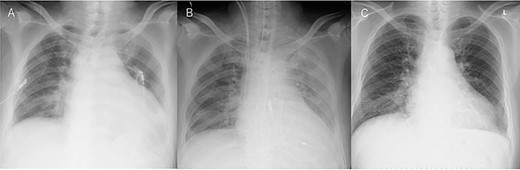

An Asian male in his 60s complained of sudden chest pain and was referred to a regional hospital. Electrocardiography showed massive ST-elevation in V1-4, and emergency coronary angiography revealed occlusion of the left anterior descending (LAD) artery (Fig. 1a). PCI was successfully performed (Fig. 1b), and IABP was inserted. Maximum value of creatine-kinase was 10 080 U/l, and his left ventricular function was severely impaired with an ejection fraction of 30%. High dosage of catecholamine was administrated and his hemodynamic status gradually recovered; however, he fell into profound cardiogenic shock on post PCI Day 6. Chest X-ray showed significant cardiomegaly (Fig. 2a), and trans-thoracic echocardiography revealed cardiac tamponade.

Chest X-ray findings. (A) Preoperative, (B) immediately after operation and (C) just after explantation of Impella.

The patient was transferred to our hospital where emergency operation was performed via median sternotomy. Oozing type LVFWR on the anterior wall was found, and was treated with a non-suture technique using TachoSil (Nycomed, Zurich, Switzerland), and without cardiopulmonary bypass. Thereafter, the IABP was removed and Impella CP was inserted percutaneously from the right groin (Fig. 2b). His hemodynamic condition recovered dramatically, and the Impella was removed on postoperative Day 5 (Fig. 2c). The patient was discharged home on postoperative Day 18, and 3 months after the onset of MI, he is doing well.